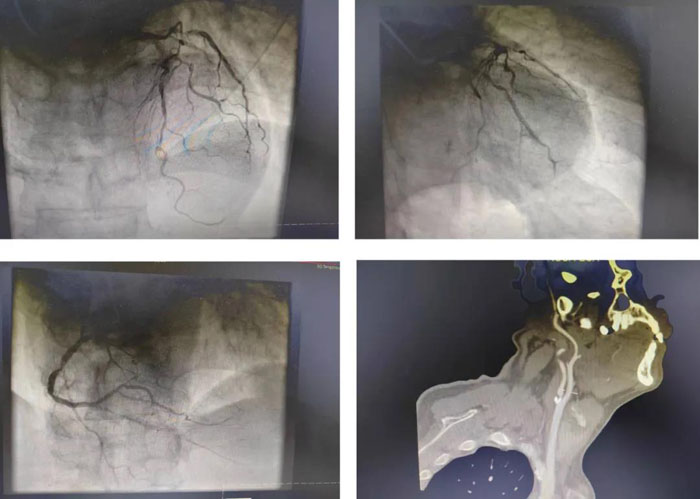

患者高先生,67歲,反復胸痛不適3天,來我院心內(nèi)科就診,行冠狀動脈造影檢查,發(fā)現(xiàn)冠心病,三支病變,不宜行介入診療,患者及其家屬同意行冠狀動脈搭橋手術,轉入心臟大血管外科。術前行頭頸部血管CTA檢查發(fā)現(xiàn)右側頸內(nèi)動脈開口處重度狹窄接近閉塞,存在頸動脈的嚴重病變,這對心臟手術的圍術期安全造成巨大威脅。

患者術前冠狀動脈造影及頸部血管CTA